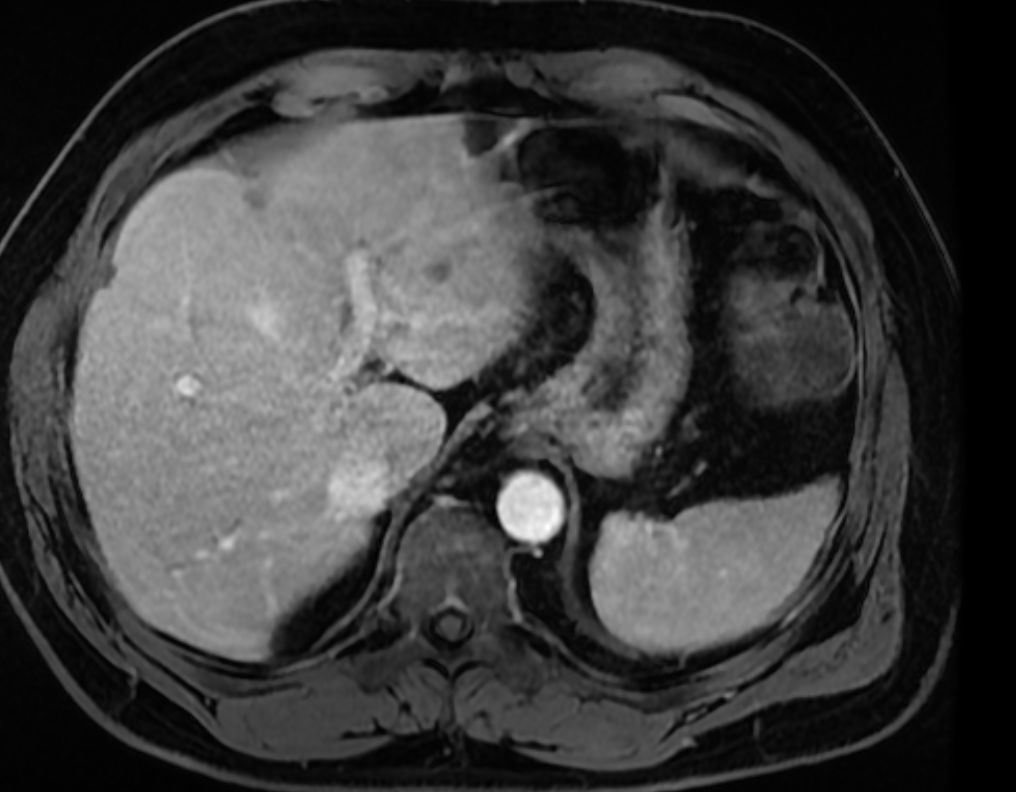

Методы динамического контрастирования печени на МРТ

Раздел: Снимки-подсказки